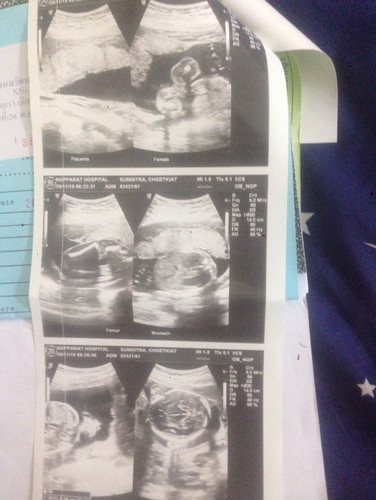

ภาพลูก

ดูยังไงคะ. ดูไม่เป็นเลยค่ะ ไม่รู้ว่าอันไหนตัวลูก 21w6b แม่ๆช่วยดูให้หน่อยค่ะ❤️

ภาพฝั่งขวาล่างและกลางหมอถ่ายศรีษะน้องค่ะ

ขอบคุณค่ะ🙏